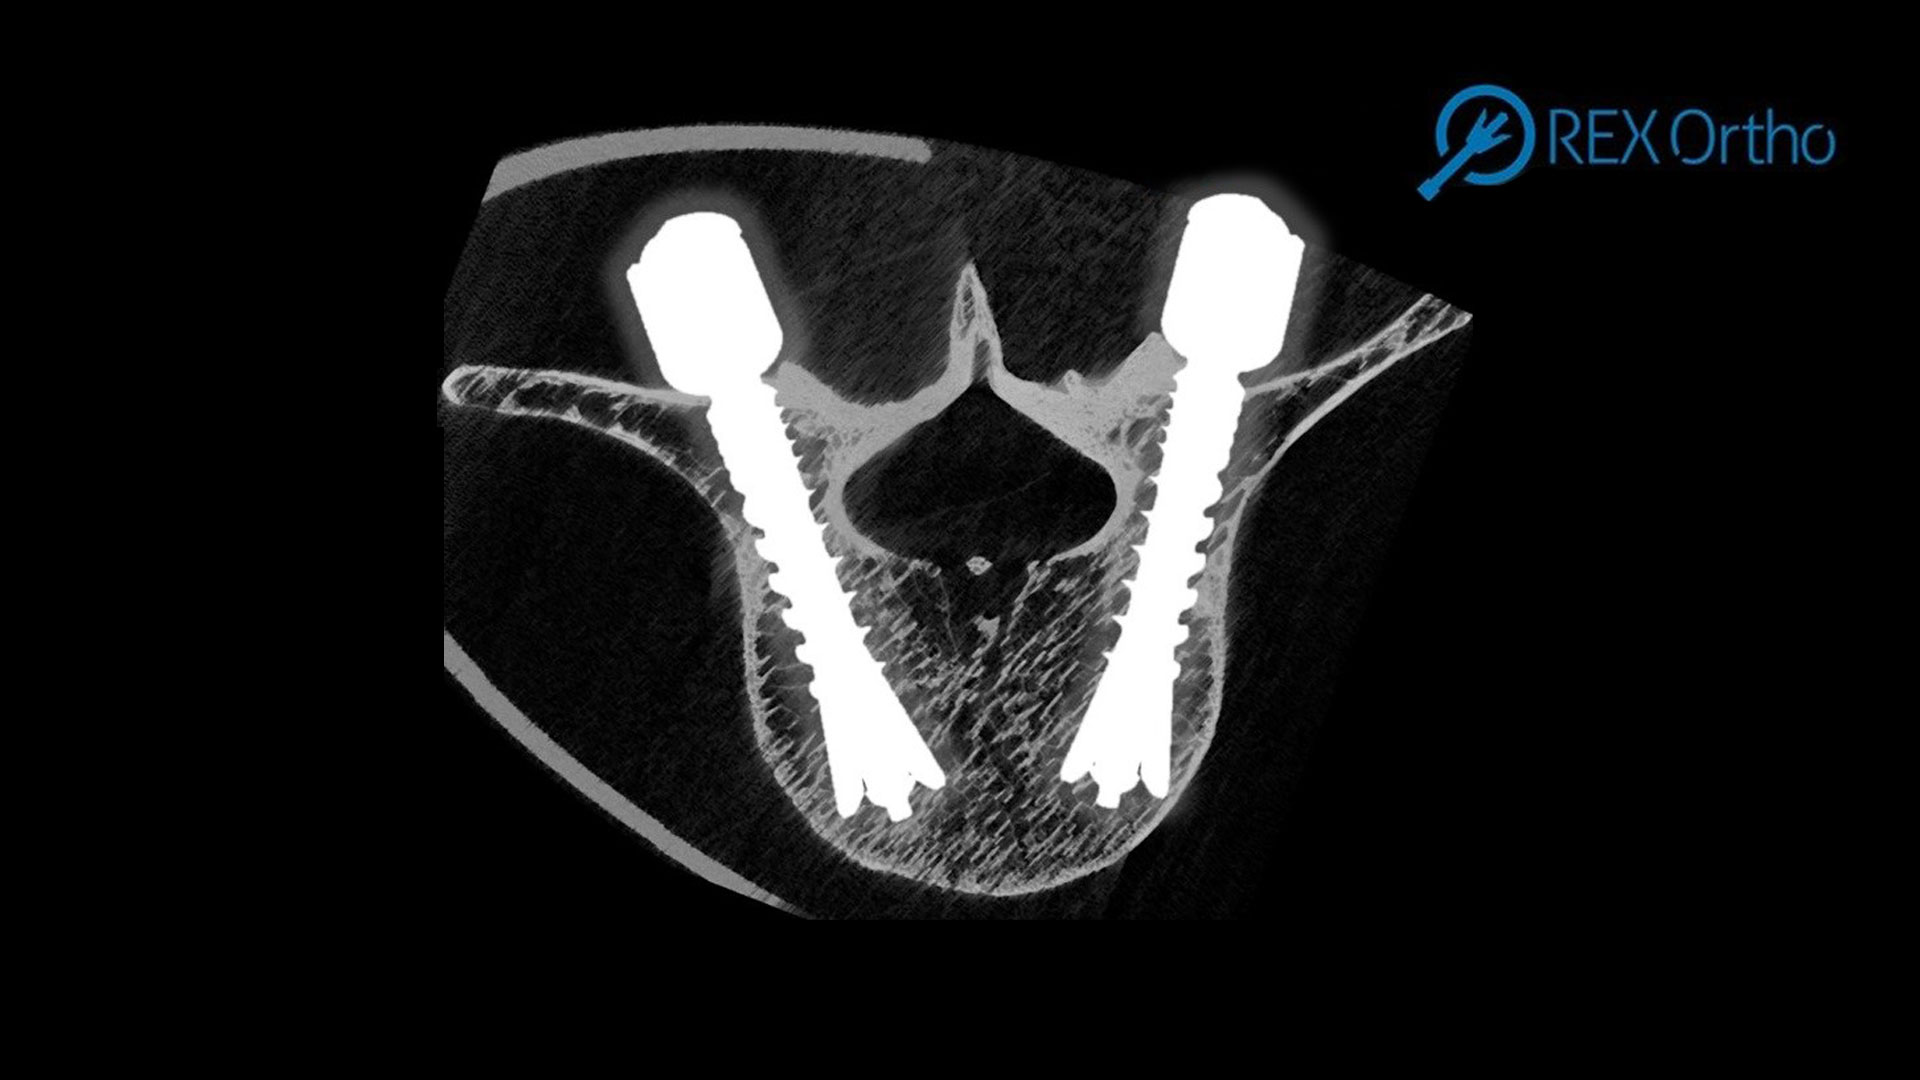

A new spinal screw offering better fixation, stability, and—uniquely—removability could be in surgeons’ hands in the next four to five years, thanks to the collaboration of AO’s innovation funding and the Australian company REX Ortho. The S-REX Screw project, which got underway in late 2023, brings together the AO, REX Ortho, and Switzerland’s 41medical to collaborate to apply novel fixation technology and develop a new spinal screw. The AO—with its global network of over half a million health care professionals—will support the project with input on clinical usability, biomechanical know-how, clinical trials, market access, and funding; 41medical will contribute expertise in regulatory clearance, prototyping, manufacturing, and more. REX Ortho Executive Chair Ian Brown said the S-REX pedicle screw—the latest innovation in the company’s platform technology—is targeting a design that will provide a clinically meaningful increase in...